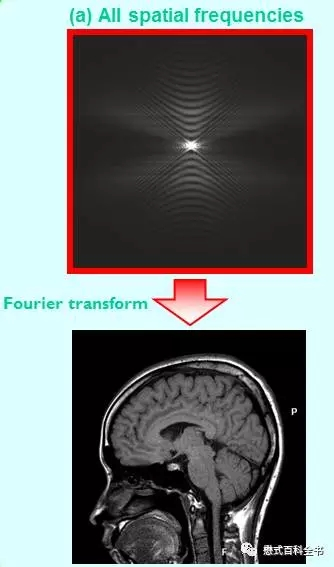

图13:把K空间所有的信息(中央部分和周边部分)都利用,重建后的图像是一个完整的图像。对比度和解剖细节都很好。